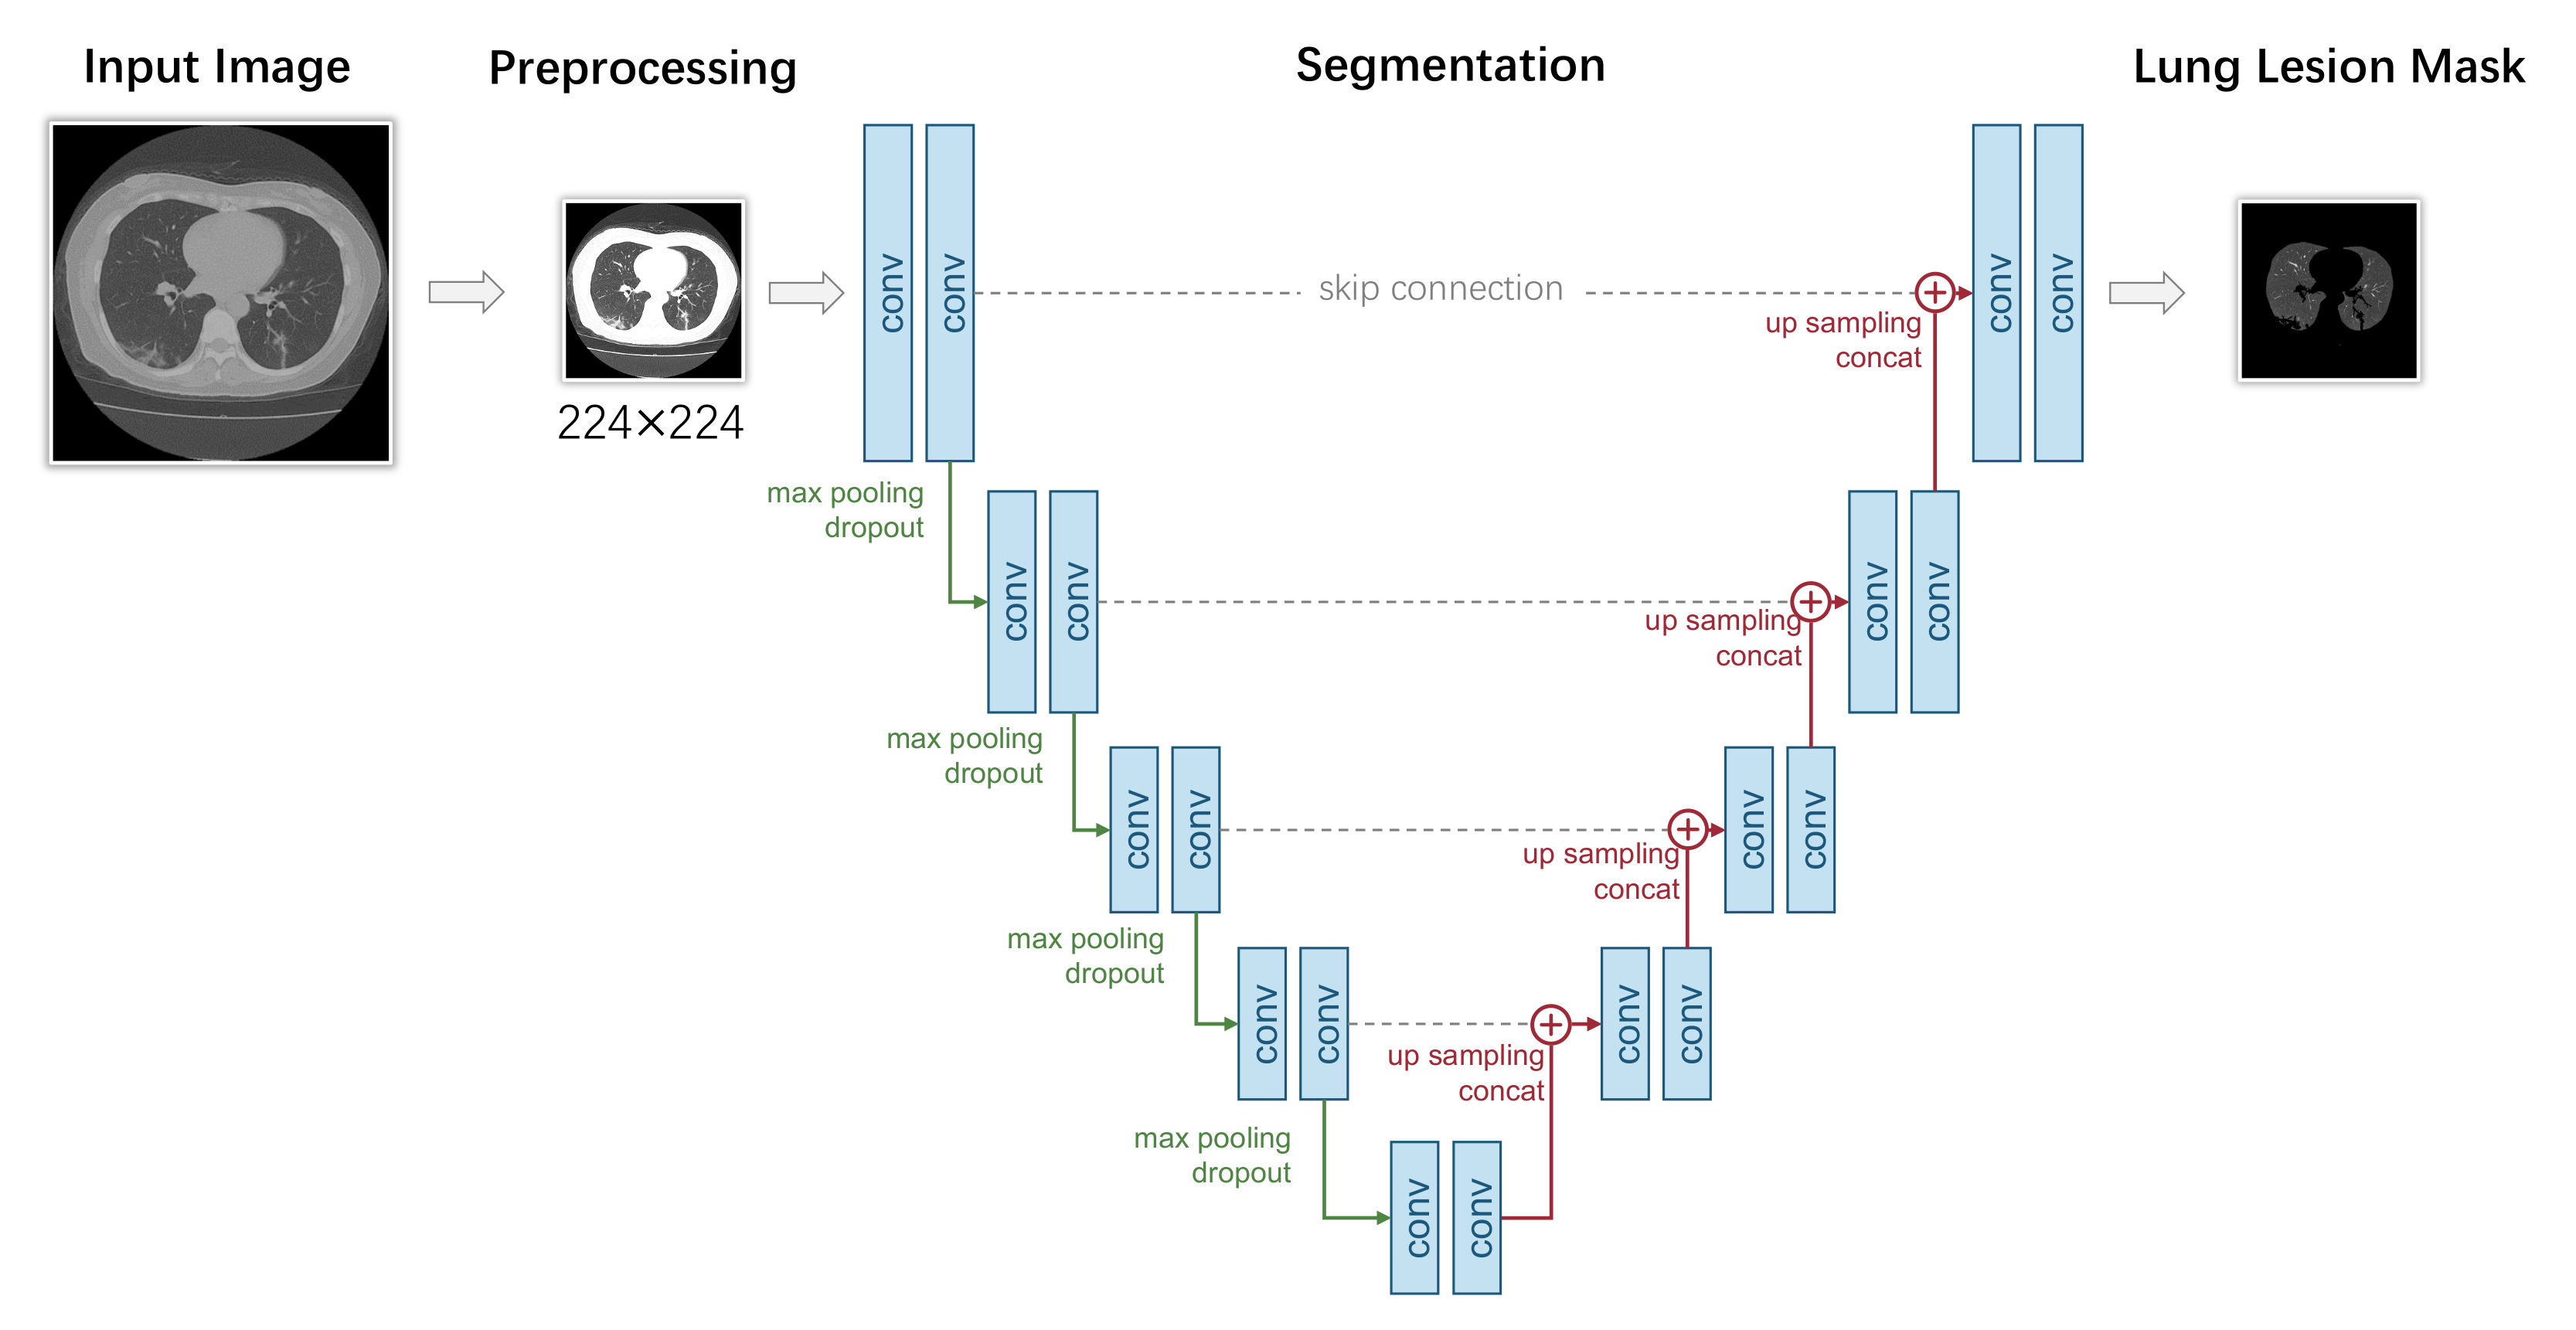

3.2. Pixel-Level Diagnosis: Segmentation-Based Models

3.2.1. Overview

3.2.2. Preprocessing

3.2.3. Segmentation

3.2.4. Evaluation